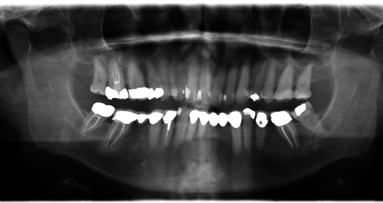

We began by completing the conventional clinical and radiographic examination. Clinically his ridge appeared narrow in the area of tooth #28 and #29, but crestal tissue was keratinised (Figs. 1–3). The patient travelled well over an hour to visit our office and he was aware that we are a proponent of performing flapless guided implant surgery when possible. I explained the benefits and risks associated with this type of implant surgery. The advantages include fast, safe, accurate implant placement with a minimally complicated post-op healing period. Digital 2-D periapical X-rays taken were limited in their diagnostic value. There was no way to be certain as to the exact location of the inferior alveolar nerve or the lingual concavity in the molar area. With that in mind we discussed, and he agreed to accept a CBCT scan to fully evaluate his current condition and determine if enough bone volume existed to perform a guided implant surgery.

This is where my in office CBCT unit becomes invaluable as the information cannot be obtained by any other in office radiographic modality. A medical CT could be requested which exposes the patient to a much larger dose of radiation and could only be taken at a different imaging center. Obviously I could not treat the patient if the existing bone anatomy was deficient and could not accept a properly positioned root form dental implant in solid bone. He was thinking that he could replace four teeth with two implants and a bridge. But that was not appropriate due to the large mesial distal edentulous span of missing teeth. The crest in the area of tooth #29 and #30 exhibited height and labial bone loss. Due to his occlusion, number of missing teeth and the position in the lower right dental arch, I felt it would be necessary to place a minimum of three fixtures to retain a 4-unit fixed bridge.